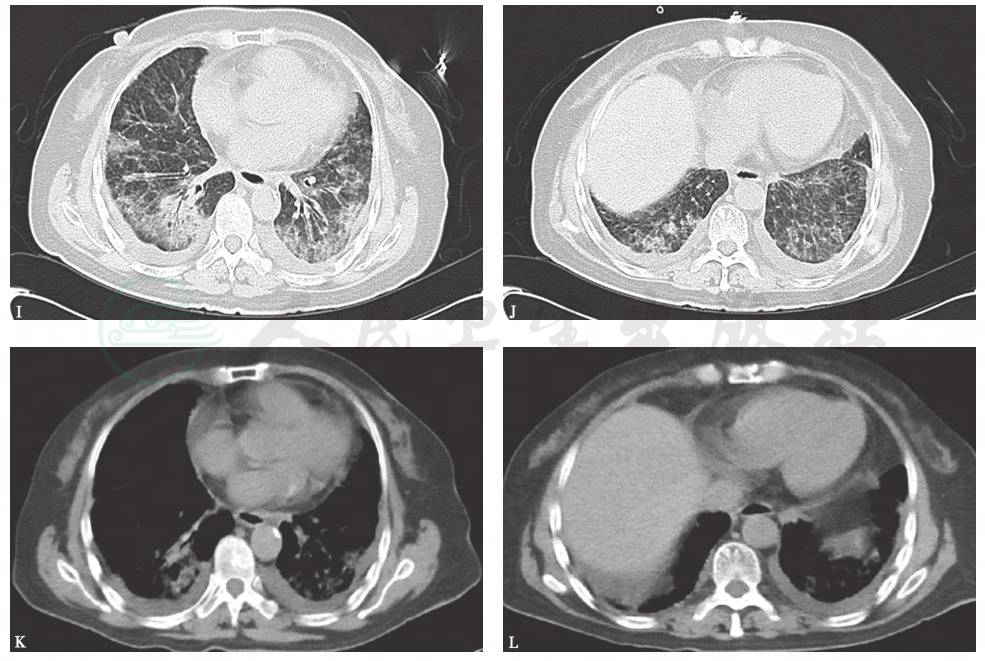

胸部X线检查可见双肺弥漫高密度影,双侧少量胸腔积液(图4),1个月后病灶进一步增多、加重(图5)。胸部CT显示病灶进一步融合增多,伴双侧胸腔积液和心包积液(图6)。

图6 胸部CT表现(2015-06-03)

胸部CT可见双肺多发斑片影、结节影,双侧少量胸腔积液,少许心包积液